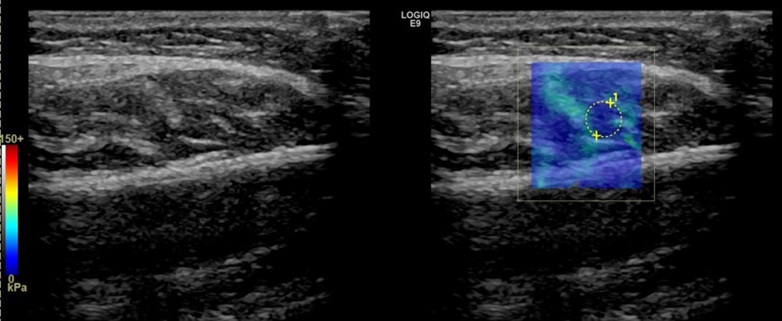

Myofascial pain is one of the common symptoms in patients with temporomandibular joint disorders (TMD). Occlusal splint (OS) and masticatory muscle trigger point (TP) local injections are primary treatment options. We aimed to investigate the effects of these treatments using clinical and elastography measures. Patients who were diagnosed with myofascial pain according to Diagnostic Criteria for Temporomandibular Disorders (DC/TMD) were included. There were 16 patients in each group. Group 1 was treated with occlusal splint, Group 2 was treated with occlusal splint and masseter muscle lidocaine injection, Group 3 was treated with masseter muscle lidocaine injection and Group 4 consisted of healthy volunteers. Degree of pain and maximum mouth opening (MMO) were recorded. Masseter muscle stiffness was evaluated by Shear wave elastography. Measurements were repeated at 1st and 3rd months of post-treatment. Pain decreased at all times in all the patients (p = 0.001). Pain in Group 2 and Group 3 approached 0 level at 3rd month. MMO increased from baseline to 1st month and from 1st month to 3rd month and masseter stiffness decreased from baseline to 1st month and to 3rd month (p = 0.001) in all groups. Occlusal splint and masseter muscle lidocaine injection were effective in reducing pain and increasing MMO in patients with myofascial pain. All treatments reduced masseter muscle stiffness. All the treatment modalities had clinically similar and successful outcomes.